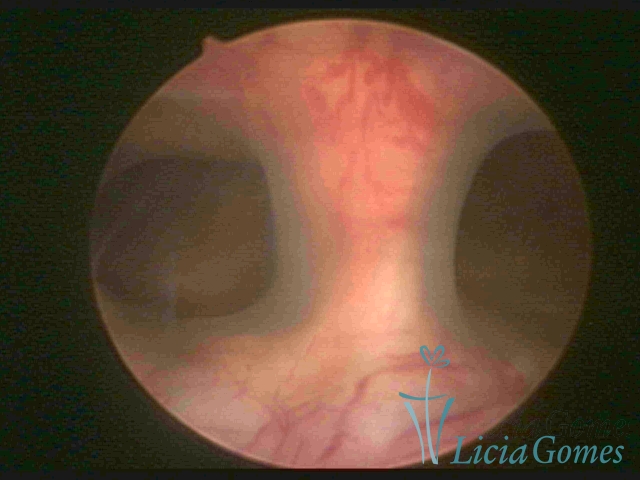

Bicornuate uterus

Malformation in which there is the lack of the flat portion of uterine fundus due to the lack of fusion on the proximal portion of paramesonephric ducts. The uterine fundus has two narrowed spaces in a divergent oblique angulation. It may be complete, from the fundus to the cervix; or partial, completely dividing the uterine cavity.

The tilted uterus which presents the most difficult hysteroscopic diagnosis occurs when there is only a small indentation of the uterine fundus.